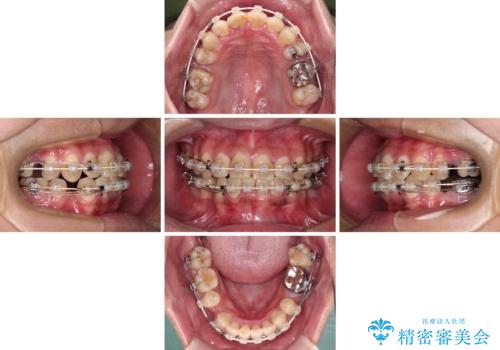

重なって磨きにくい上下の前歯 ワイヤー装置での抜歯矯正

- 前歯のデコボコを改善したいと来院された患者様です。

口元の突出感はないものの、上顎前歯のデコボコが著しかったため、上下顎左右小臼歯4本を抜歯することとしました。

上下の正中位置を改善するため、右下は第一小臼歯を、その他は第二小臼歯を抜歯することとしました。

第二小臼歯抜歯の矯正治療は、治療期間が長引くことが多いですが、動きが非常に良く、予定の治療期間で終えることができました。

上下の正中も思っていた以上に良い位置に改善されました。